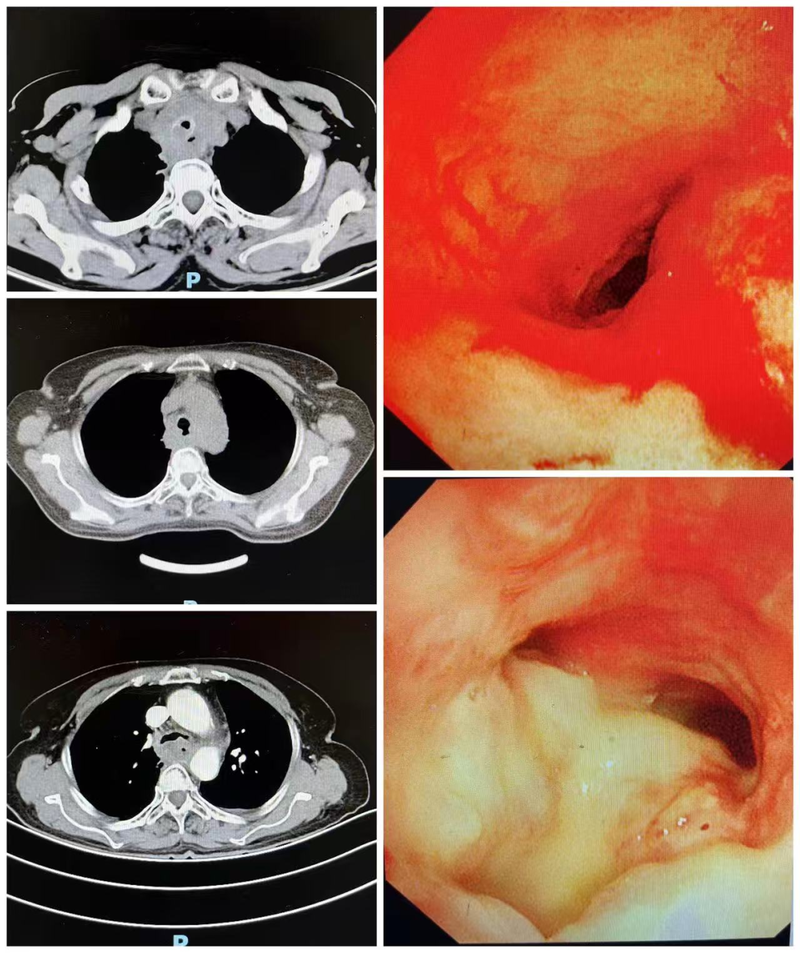

临沂市中医医院成功实施Y型支架置入术,封堵瘘口畅通呼吸

近日,临沂市中医医院解放路院区肺病二科(呼吸与危重症医学科)主任医师耿玉青与麻醉副主任医师黄振强带领团队紧密协作,成功为一名因食管肿瘤导致恶性气道狭窄并伴有气管食管瘘的患者,实施了硬质气管镜下Y型金属